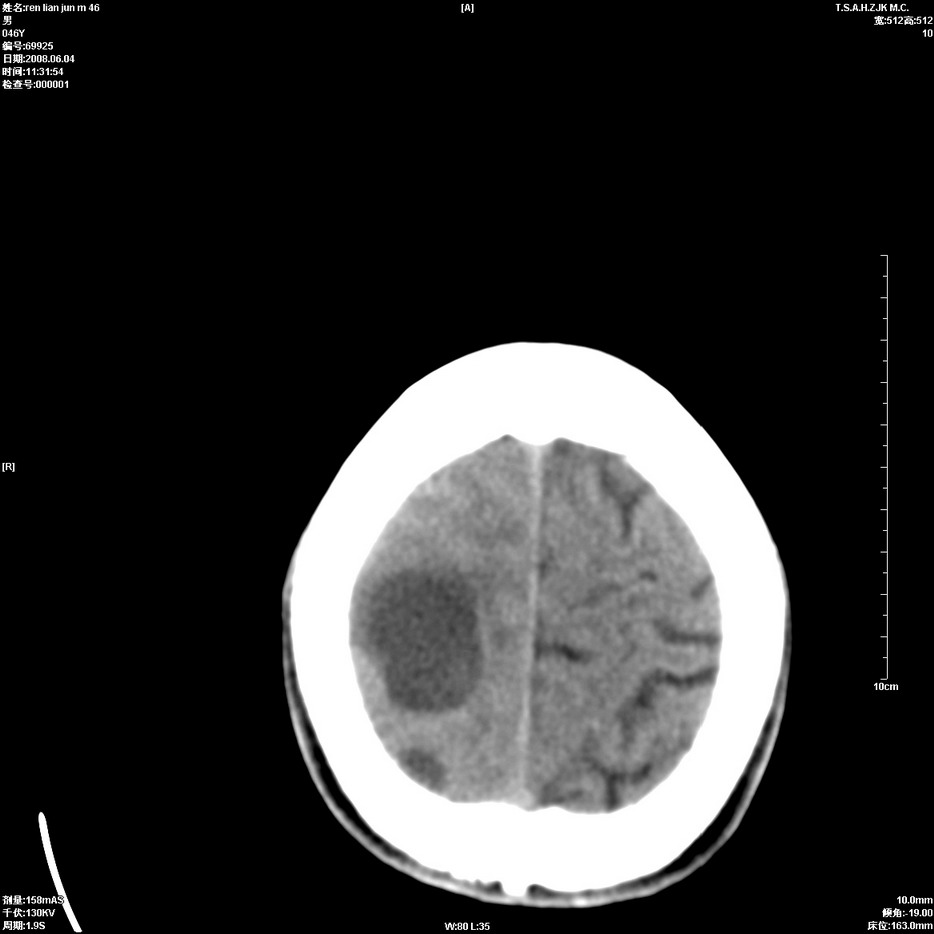

以下是引用qiu999在2008-6-5 17:14:00的发言:[br]考虑右肺中心型肺癌.颅内应做增强检查.

以下是引用形影不离在2008-6-5 19:18:00的发言:[br]右肺中心型肺癌并纵隔及左侧腋窝淋巴结转移,颅内应做增强检查。

以下是引用杀毒软件在2008-6-5 18:33:00的发言:[br]支持考虑右肺中心型肺癌,颅内病变是不是转移,不好说